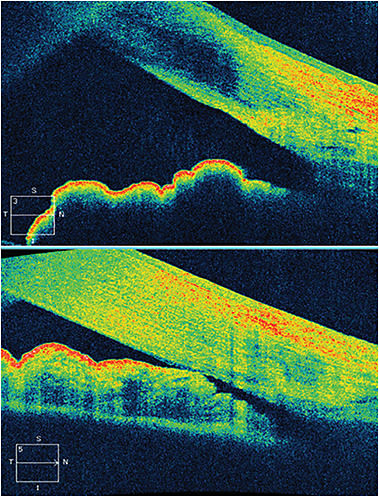

Angle closure is an important and often undetected cause of blindness from glaucoma. In China, as of 2001, there were an estimated 28 million people with occludable angles, with 91% of the glaucoma-related blindnesses caused by angle closure.11 (See chart, page 10.) One could argue there is no less expensive but more powerful tool, providing such a high payoff for patient care, than gonioscopy, although OCT produces fantastic images (Figure 1). Perform gonioscopy at baseline in any patient with glaucoma or suspected glaucoma or with the appearance of anterior chamber shallowing or peripheral iridocorneal narrowing. We should repeat gonioscopy more frequently in patients who are older and hyperopic.

Figure 1. While gonioscopy remains the gold standard, optical coherence tomography can provide objective and illustrative characterizations of the angle. The top image demonstrates a normal, open angle while the bottom image demonstrates a closed angle with iris in contact with the peripheral cornea.

COURTESY: NATHAN M. RADCLIFFE, MD